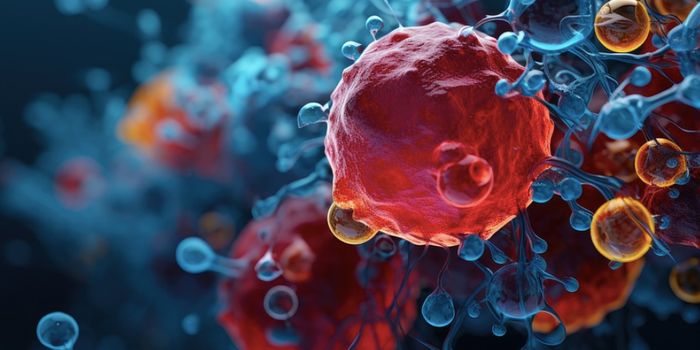

JUN 29, 2017CancerMost cancers kill by invading distant parts of the body where treatment is more difficult to reach. But cancer’s a ...

OCT 19, 2017CancerTo fuel their growth and edge out healthy cells, breast cancer cells recycle a waste product into nutrients, researchers ...